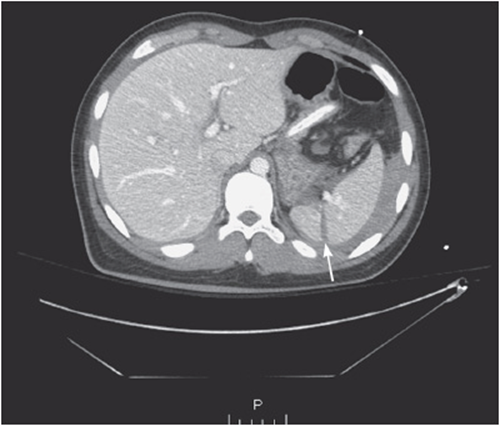

iii. Look for free fluid and intra-abdominal fluid collections:

• Free fluid in the abdomen is an abnormal finding and can be seen anywhere in the abdominal cavity (see Figure 56-3).

Figure 56-3. Free fluid.

• It most commonly represents blood, pus, ascites, or enteric contents.